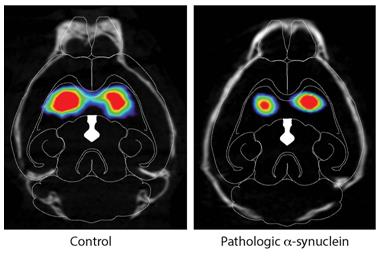

帕金森病致病在小鼠體內的傳播途徑。圖片來源:Ted Dawson

右圖為α-突觸核蛋白注入小鼠腸道后的DAT掃描,左圖為對照組。圖片來源:Ted Dawson

為了驗證這一點,在最新的研究中,Ted Dawson博士和他的同事HanseokKo博士等將實驗室中合成的錯誤折疊的α-突觸核蛋白注入數十只健康小鼠的腸道中,并對注射后1個月、3個月、7個月和10個月的小鼠腦組織進行取樣和分析。在為期10個月的實驗過程中,研究人員發現,α-突觸核蛋白開始在迷走神經與腸道相連的地方積聚,并繼續擴散到大腦。

研究人員隨后切除了一組小鼠的迷走神經,并將錯誤折疊的α-突觸核蛋白注入其內臟。經過7個月的觀察,研究人員發現,迷走神經斷裂的小鼠沒有發現細胞死亡的跡象。Dawson表示,切斷的神經似乎可以阻止錯誤折疊的蛋白質的進展。